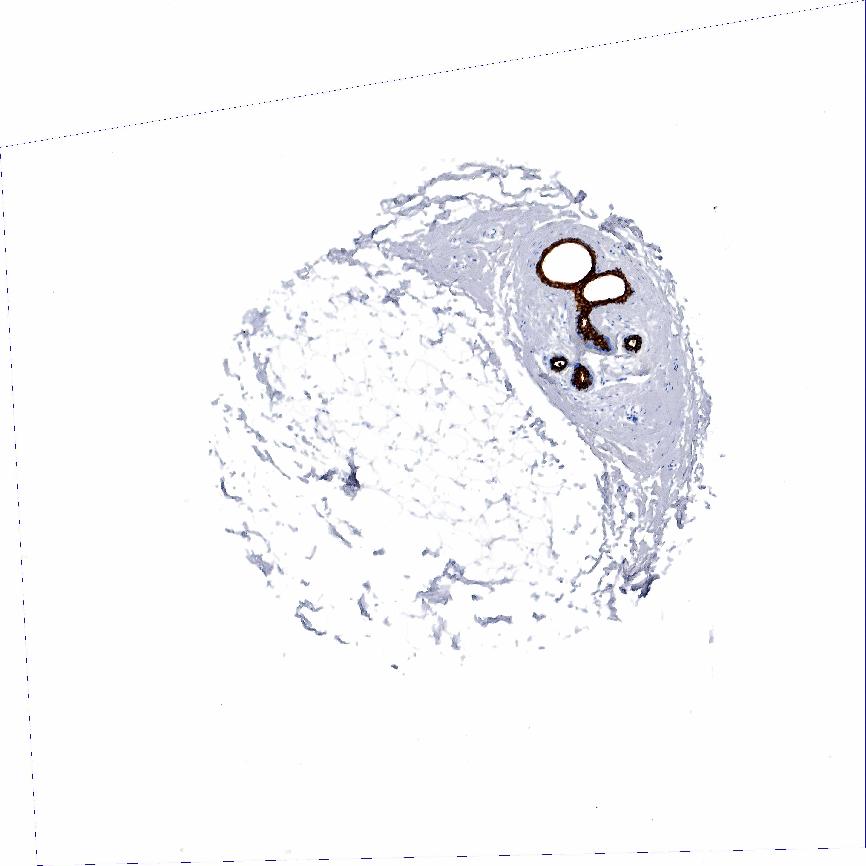

ADIPOSE TISSUE - Antibody stainingi

Antibody staining in the annotated cell types in the current human tissue is reported as not detected, low, medium, or high, based on conventional immunohistochemistry profiling in selected tissues. This score is based on the combination of the staining intensity and fraction of stained cells.

Each image is clickable and will lead to virtual microscopy that enables deeper exploration of all samples and also displays staining intensity scores, fraction scores and subcellular localization as well as patient and tissue information for each sample.

Antibody HPA002465Antibody CAB000031

Adipocytes Not detectedNot detected